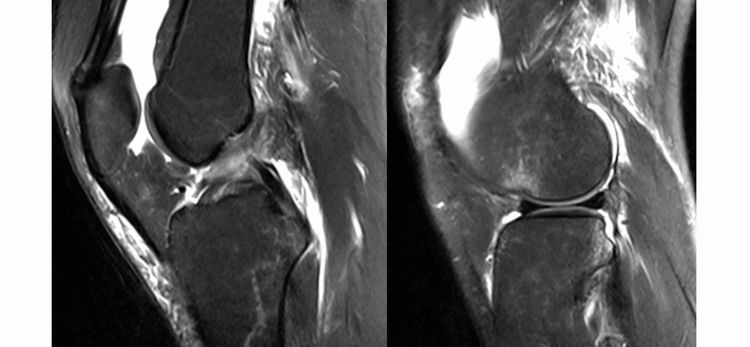

ACL损伤的直接征象:指ACL本身的形态和信号异常。一旦有了明确的直接征象就可以确定ACL损伤。

1.不连续:有韧带的低信号,但中断不连续。一般见于新鲜损伤。

2.方向异常(ACL 下垂征):有较完整的韧带低信号,但方向异常,呈下垂状。一般见于股骨附着部的陈旧损伤,损伤的ACL下垂并粘附在PCL上。

3.ACL 消失:髁间窝空虚,无韧带信号。见于较久的损伤,损伤的ACL撕裂较重呈马尾状,无滑膜包裹,逐渐被关节内的酶腐蚀而消失。

4.撕脱骨折:一般为ACL胫骨附着部的撕脱,韧带完整,信号多正常。

5.假瘤:韧带损伤后断端较整齐,残端组织增生并被滑膜包裹呈"瘤状",如果突出于前方为"独眼征",多见于韧带股骨附着部撕裂及部分撕裂。

6.扭曲和空虚:髁间窝内似隐隐约约有低信号,边缘明显,中央空虚;或者中央有低信号,但扭曲如麻花状。多为陈旧损伤,仅存ACL的滑膜,里面可有少量的韧带纤维,粘附在后方,随着膝关节的长时间屈伸逐渐呈扭曲状。